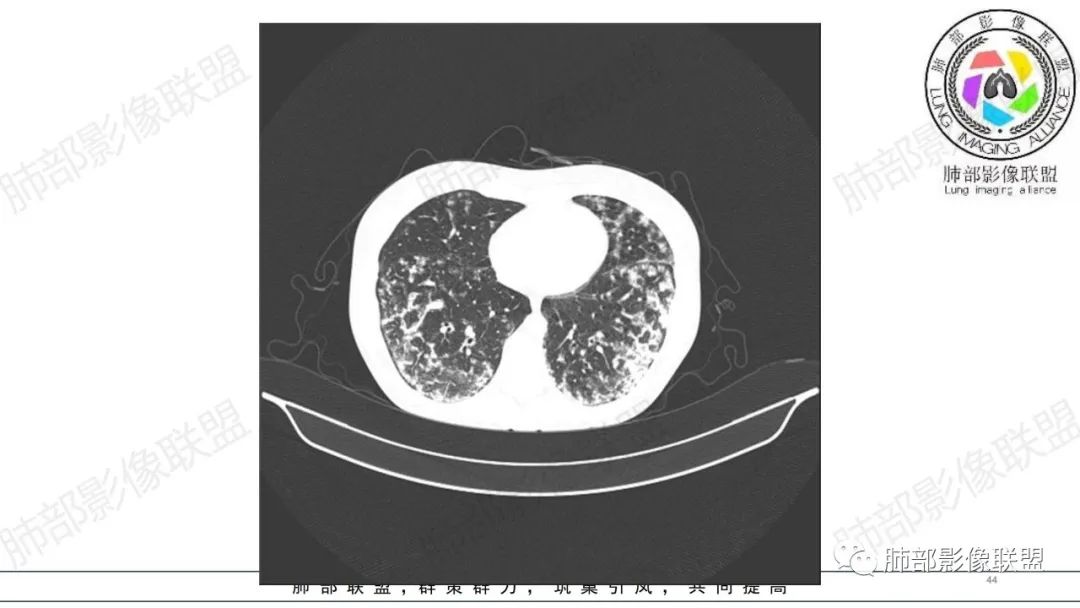

34岁女性患者,“哮喘”病史30年,近期有可疑刺激性气体吸入史;因乏力半年,咳嗽、憋气、发热4天就诊;6.1CT提示双肺广泛毛玻璃影及粟粒样结节,胸膜下闲置及血管周闲置,可见树丫征,部分小叶间隔增厚。考虑:1.过敏性肺泡炎,有可疑刺激气体接触史,胸膜下闲置,广泛毛玻璃影,地图样分布,粟粒结节边界模糊,支持过敏性肺泡炎,但糖皮激素治疗效果不佳,且动态复查血常规血红蛋白进行性降低,过敏性肺泡炎 不符合;2.肺含铁血黄素沉积症:患者30“哮喘”病史,可能为肺含铁症状,肺部CT提示双肺弥漫毛玻璃影及粟粒结节影,中下肺明显,肺底部分小叶间隔增厚,近期咳嗽、憋气、发热,血常规血红蛋白进行性下降,考虑肺含铁急性期症状,但临床无咯血症状,肺含铁不典型。综合考虑:肺含铁血黄素沉积症>过敏性肺泡炎。

年轻女性 ,急性喘息发热,肺部影像弥漫磨玻璃密度,部分细小腺泡结节,胸膜下黑线显示,短期复查,病变密度增高,下肺明显,血管周围肺组织累及较少、且逐渐成小叶间隔分布。考虑弥漫肺泡内病变,并经淋巴道转移,下肺比上肺明显,多为免疫细胞功能下肺较强。1.过敏性肺泡炎,有相关病史,三层密度特点、头尾测分布,符合。2 肺泡微石症,多有钙化,且缓慢起病,病程不太符合,放待排。3 吸入相关肺损伤,有病史,疾病演变过程也符合渗出-肉芽肿改变,建议详细询问病史。4 感染性病变,结核?病变气道分布为主,如此弥漫且没有树丫不符合。5.巨细胞病毒,可以磨玻璃 结节 改变,没有免疫缺陷病史。最后考虑吸入所致 1过敏性肺泡炎、吸入性肺损伤 鉴别肺泡微石症。

肺内气腔磨玻璃结节,肝脾肿大,治疗后间质改变,弥漫大B可能